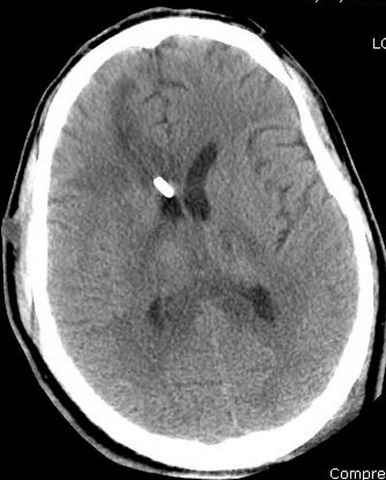

больному 42, автоавария, политравма, открытая черепномозговая травма, безсознании, открытый перелом бедра, размозжение мягких тканей, дефект кожи на передней поверхности бедра около 13 см2 от ожога, компартмент синдром.

Наблюдается службой травмы и нейрохирургии (ICP) Increased Intracranial Pressure by ventricular cateter